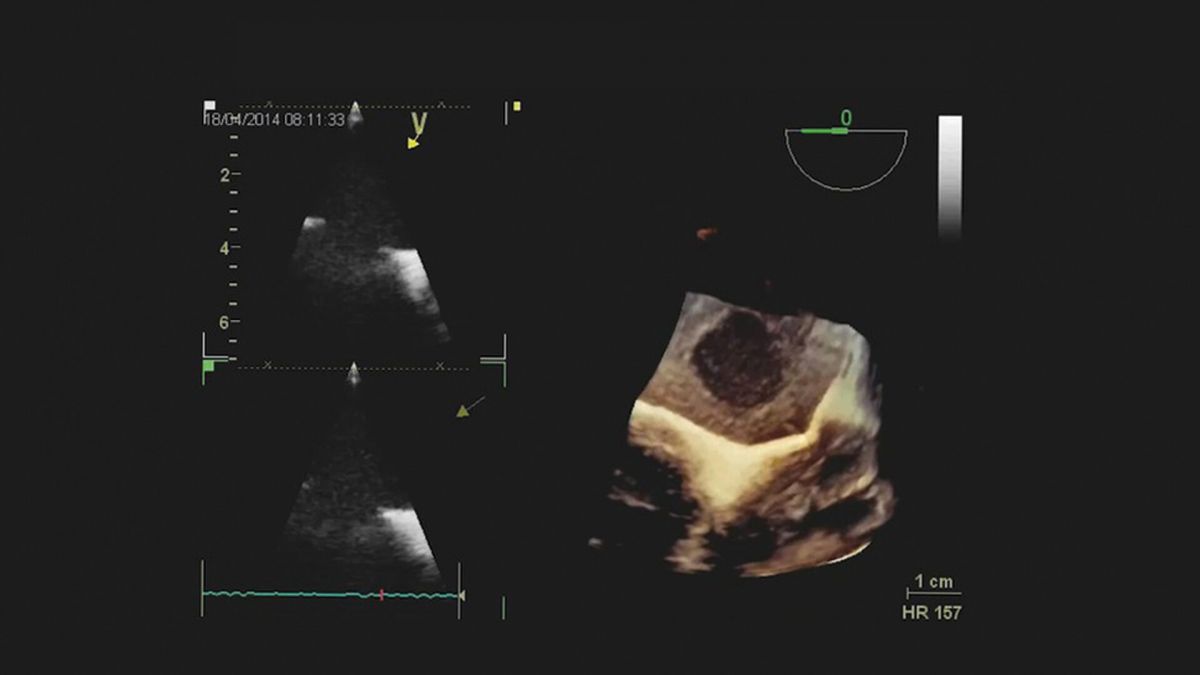

Ubytek w przegrodzie międzyprzedsionkowej typu otworu wtórnego

Ubytek w przegrodzie międzyprzedsionkowej typu otworu pierwotnego

Drożny otwór owalny

Echokardiografia przezklatkowa i przezprzełykowa

Ocena ubytku w przegrodzie międzyprzedsionkowej

Ocena prawych jam serca

Kwalifikacja do przezskórnego zamknięcia ubytku w przegrodzie międzyprzedsionkowej

Kwalifikacja do leczenia operacyjnego ubytku w przegrodzie międzyprzedsionkowej